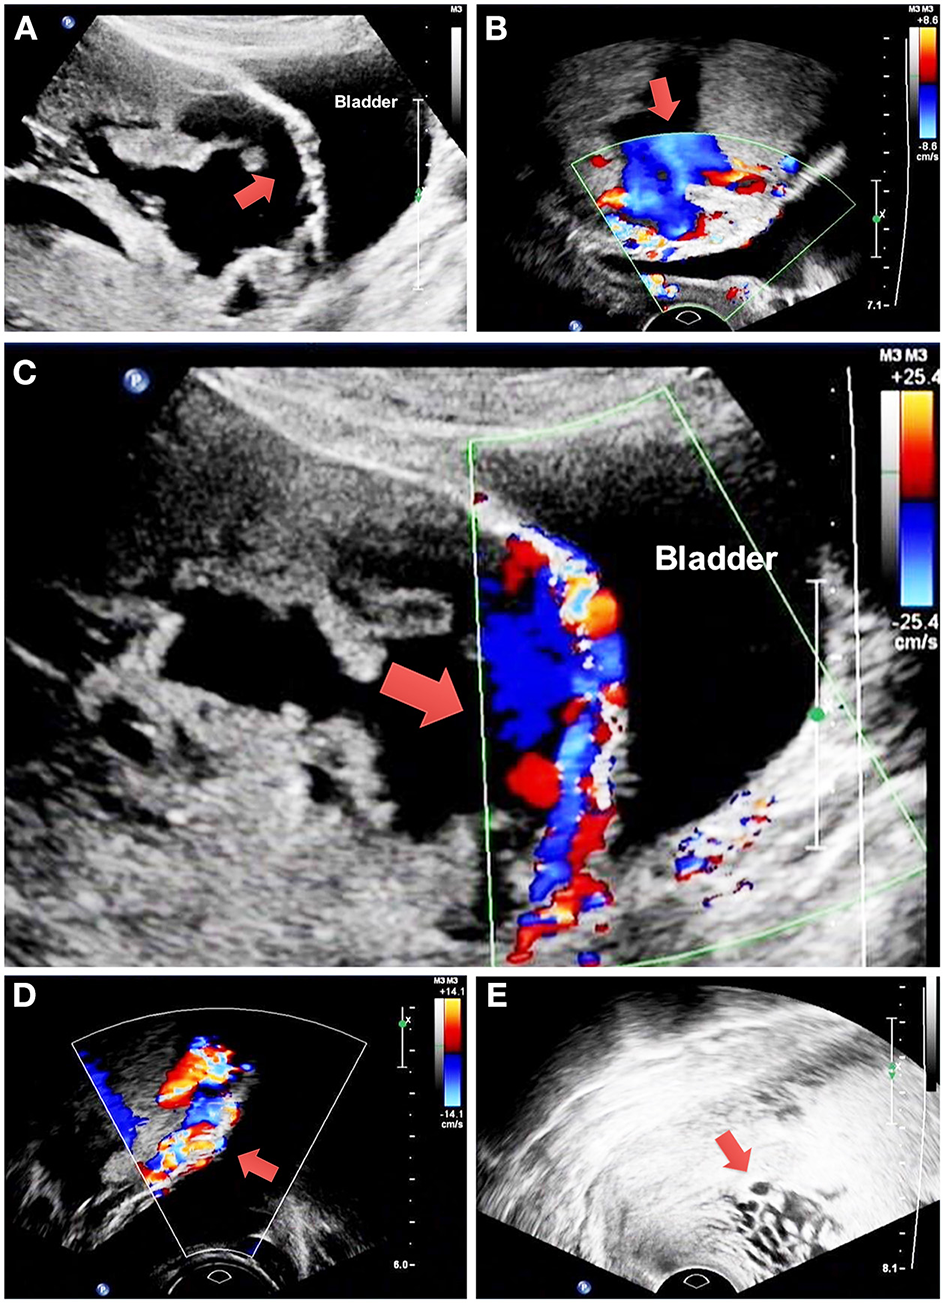

The study includes 194 and 66 patients in the non-BPAA and BPAA groups, respectively. Table 1 summarizes the characteristics of patients. Compared with patients in the non-BPAA group, a greater number of patients in the BPAA group showed abnormal placental vasculature on the preoperative ultrasonography, such as retroplacental myometrial thickness <1 mm (P = 0.002), intraplacental vascular lacunae (P < 0.001), hypervascularity of the uterine-placental margin (P = 0.090), irregularity of the uterine-bladder interface (P < 0.001), hypervascularity of the uterine serosa-bladder wall interface (P < 0.001), and the cervical hypervascularity (P = 0.011). We observed no significant intergroup differences in age, gestational age, pregnancy history, or other preoperative characteristics (P > 0.05). Figure 2 shows the Doppler characteristics of patients with severe PAS with previa.

Figure 2

Doppler findings in patients with severe placenta accreta spectrum with previa. (A) The red arrow shows retroplacental myometrial thickness <1 mm and irregularity of the uterine-bladder interface. (B) The red arrow shows intraplacental vascular lacunae. (C) The red arrow shows hypervascularity of the uterine-placental margin and uterine serosa-bladder wall interface. (D) The red arrow shows hypervascularity of the uterine serosa-bladder wall interface. (E) The red arrow shows cervical hypervascularity. PAS, placenta accreta spectrum.